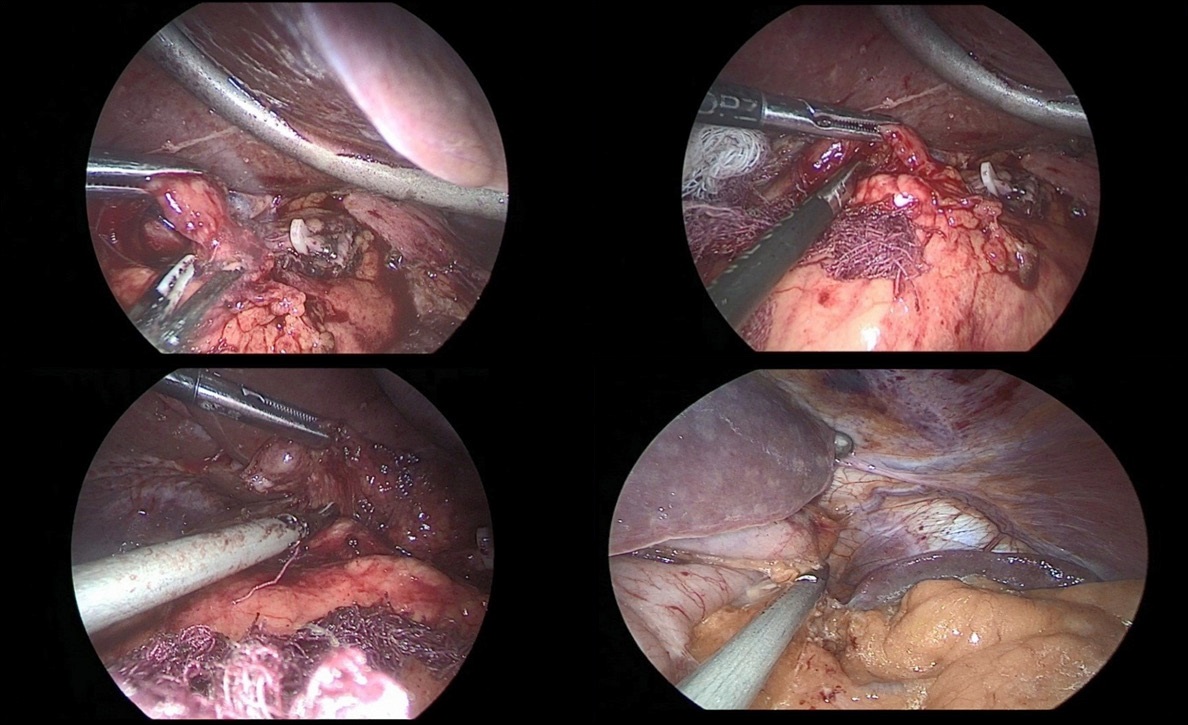

After crossing the pyloric sphincter, laparoscopic lymph node dissection of the VII, VIIIa, IX, XI, XIIa groups of lymph nodes was performed (Figure 9 a, b, c, d).

Figure 5a,b,c: Mobilization of the greater curvature of the stomach, the omental bag was opened, there was no infiltration of the serous membrane of the posterior wall of the body and the antrum of the stomach by the tumor. The right gastroepiploic artery was additionally clipped.

Figure 6a,b: Resection of the lesser omentum with removed I, III, V, VII group of lymph nodes.

Figure 7: The left gastric artery was clipped with a Hemo-Lock (X) clip, with additional fixation with tantalum clips.

Figure 8: On the antrum of the stomach, at the level of the pyloric sphincter, an Endo-Gia stapler with a 60 mm cassette was applied.

Figure 9a,b,c,d: Lymph node dissection of the hilum of the liver and celiac trunk.

Figure 10a,b: Laparoscopic omentectomy.

Figure 11a,b: Laparoscopic omentectomy.